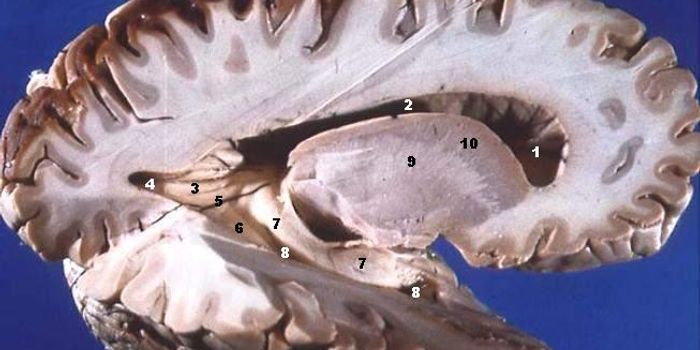

FEB 08, 2018NeuroscienceAlbert Einstein was one of the great geniuses of modern times. His accomplishments in science are second to none, and hi ...